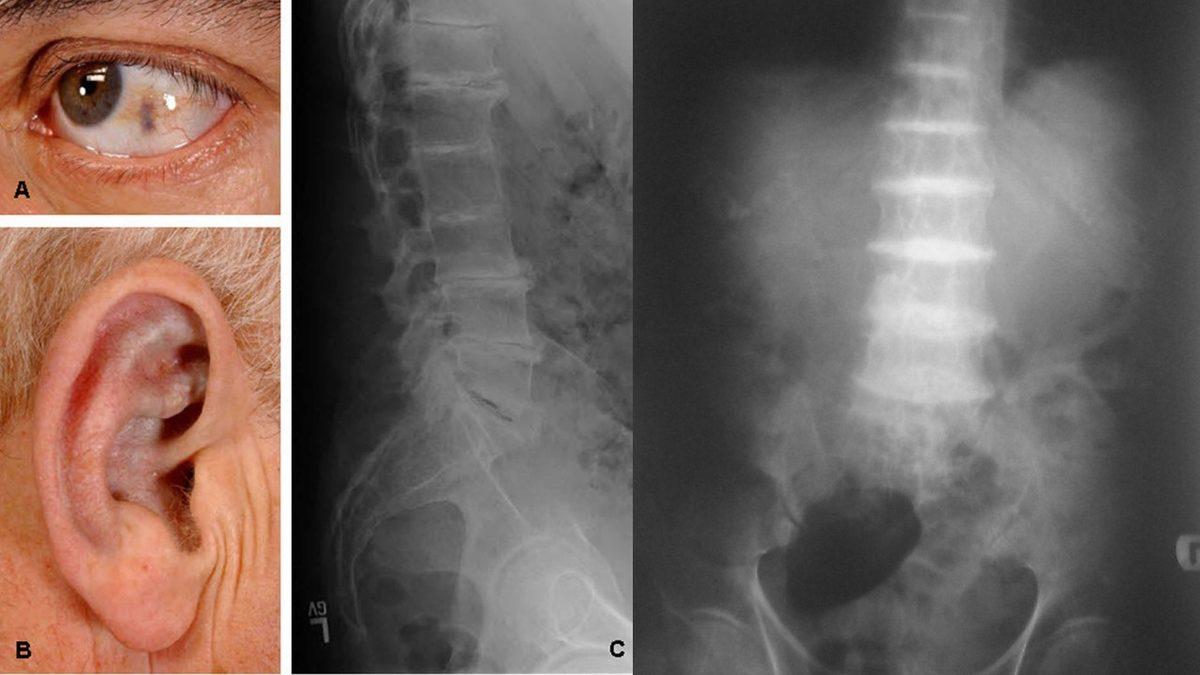

Bu hastalığa sahip kişilerde gözlerinin beyaz bölümlerinde kahverengi veya siyah noktalar gelişebilir, kulak kıkırdağında kalınlaşmalar gözlemlenip bu bölge mavi, gri ya da siyaha dönüşebilir. Aynı zamanda kulak kirinin de siyah, kahverengi ya da kırmızı olduğu görülür.

Bu asit uzun yıllar boyunca vücuttaki dokularda yavaşça birikir ve kıkırdaklar, tırnaklar, kulaklar, kemikler ve hatta kalp dahil olmak üzere vücudun hemen hemen her bölgesinden birikme eğilimi gösterir. Bu doğrultuda dokular ve vücudun bölgeleri siyaha yakın koyu bir renk alır.

Bunun yanı sıra tipik bel ağrıları ve bel bölgesinde sertlikler, diz, kalça ve omuz ağrıları görülebilirken, son raddede vücuttaki sert ve esnek bir doku olan kıkırdak kırılgan bir hale gelip, kırılabilir bu da eklem ve omurga hasarına yol açar.